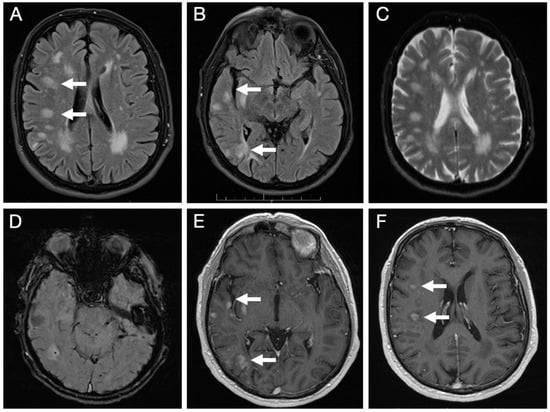

Brain MRI (Figure 3) revealed multiple lesions in the right hemisphere, involving subcortical and juxtacortical white matter and the cortical regions of all lobes, as well as the lenticular nucleus. The lesions were nodular, hyperintense on T2/FLAIR with facilitated diffusion, and showed patchy contrast enhancement. SWI sequences demonstrated areas of signal loss compatible with chronic microhemorrhages. Systemic evaluation was negative.

Figure 3.

Initial brain MRI on axial FLAIR sequences shows multiple foci of hyperintense signal abnormalities in the subcortical and juxtacortical white matter of the right hemisphere (A,B); with facilitated diffusion (C); areas of signal loss compatible with microhemorrhages on SWI sequence (D); and patchy, nodular enhancement on post-contrast T1-weighted images (E,F).